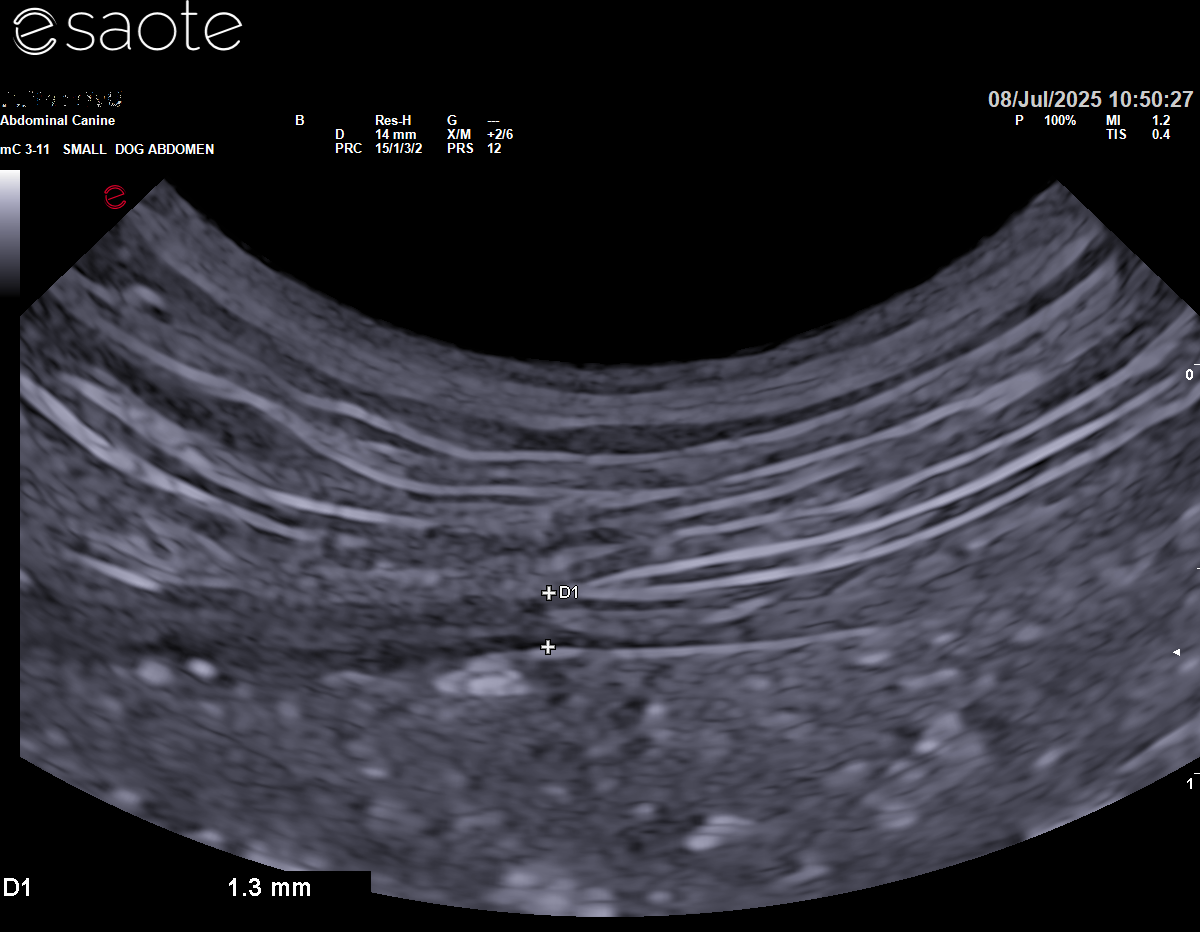

Images from the Heron

The microconvex probe is a joy to use. It will comfortably handle everything from basic to advanced abdominal scanning, and even basic cardiac work - though it’s worth noting there’s no continuous wave Doppler, so for full cardiac workups you’d still need a phased array probe. The phased array probes do offer continuous wave Doppler on this machine.

The Esaote MyLab Heron feels like a machine that’s been designed by someone who actually scans. It’s quiet - whisper quiet - even when working hard. The colour flow mapping on abdominal settings is exquisite: it’s like watching the vessels being painted on with a fine brush. Precise, clean, and confidence-inspiring. If you’ve ever struggled to interpret swirly, chaotic colour Doppler, you’ll immediately notice the difference.